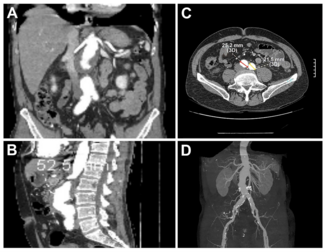

A 65-year-old man with a medical history of coronary artery disease (6 stents) and prior left femoral-popliteal bypass presented for routine abdominal aortic aneurysm (AAA) surveillance. Computed tomography angiography (CTA) demonstrated a 5.2-cm juxtarenal AA—a 5-mm increase over 6 months—along with bilateral common iliac aneurysms (Figures 1 and 2). Following a multidisciplinary evaluation, the patient was selected for treatment using the Thoracoabdominal Branch Endoprosthesis (TAMBE) device (W. L. Gore & Associates, Inc.).